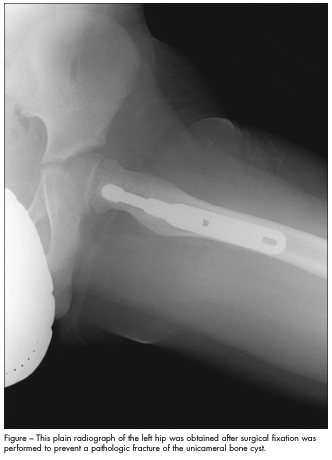

Based on the size of the lesion and its location at the femoral neck, fixation was recommended to prevent a pathologic fracture, as well as curettage and allograft to eradicate the cyst. A pathological specimen obtained at the time of surgery showed benign fibro-osseous tissue consistent with unicameral bone cyst (UBC).

At follow-up 1 month later, the boy had no pain, could ambulate without crutches, and could bear all his weight on his left leg for a few seconds. A radiograph showed a barely visible cyst outline with good homogeneity throughout the femur (Figure). He was allowed to return to all activities 2 months after surgery.